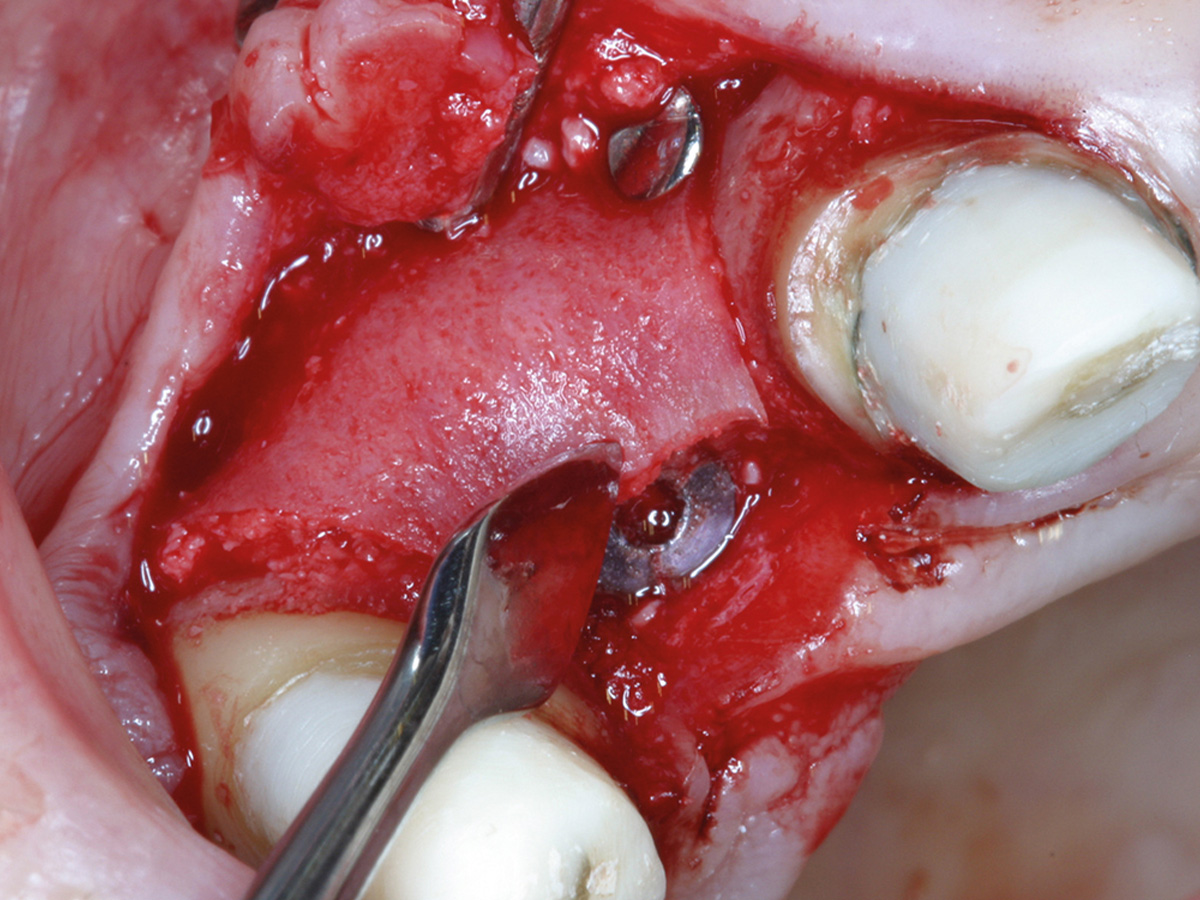

Intraoperative Situation mit koronaler Knochenbrücke und extraalveolär imponierendem Implantat (Biomet 3,2 x 13).

Abbildung 5a

Intraoperative Augmentation...

Abbildung 5b

nach Anfrischung des ortsständigen Knochens mit Bone Lamina/mp3...

Abbildung 5c

sowie Nagelung mit Frioss-Nägeln.